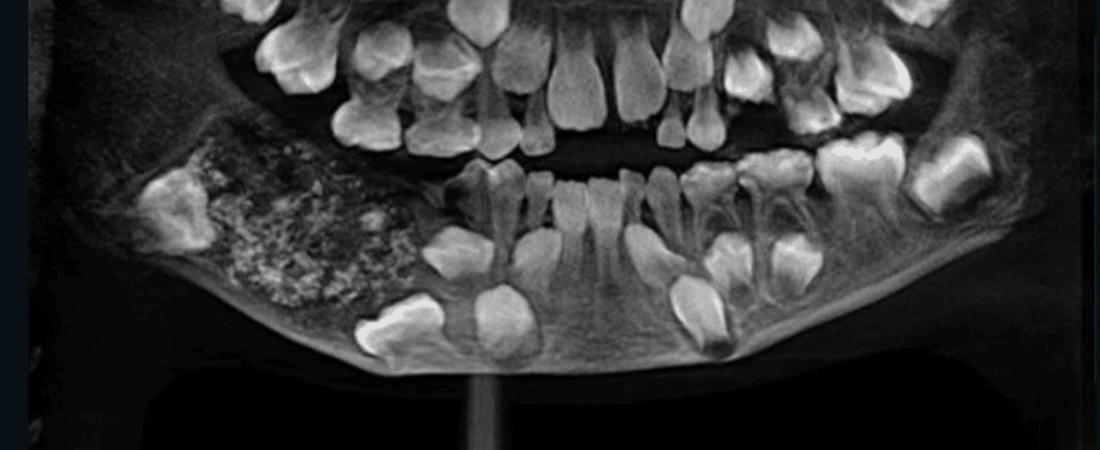

«Cuando los médicos escanearon y le tomaron radiografías de la boca, encontraron un saco incrustado en su mandíbula inferior lleno de «dientes anormales», dijo a CNN el Dr. Prathiba Ramani, jefe de Patología Oral y Maxilofacial del Saveetha Dental College and Hospital.

El equipo de Ramani tardó de cuatro a cinco horas en vaciar el saco para confirmar su contenido y descubrió los cientos de dientes.

«Había un total de 526 dientes que iban desde 0.1 milímetros hasta 15 milímetros. Incluso la pieza más pequeña tenía una corona, raíz y capa de esmalte que indicaban que era un diente», dijo.

Ramani dijo que el niño padecía una condición muy rara llamada odontoma compuesto.